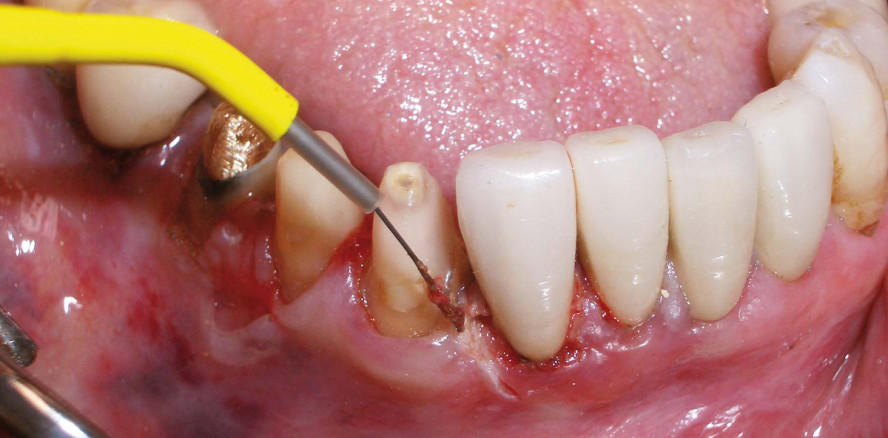

Die HF-Technologie ist einfach und klinisch bestens erprobt. Eine dünne Elektrode aus einer speziellen Metalllegierung leitet elektromagnetische Wellen ins Gewebe. Hierdurch platzen – auf makroskopischer Ebene – die Gewebezellen, was sich nach außen als minimalinvasiver Schnitt darstellt. Dieser Schneidevorgang erfolgt absolut drucklos und ermöglicht ein präzises und nahezu athermisches Schneiden von Weichgewebe. Das speziell beim hf Surg mitgelieferte Handstück ist extrem leicht und hat eine hervorragende Haptik, mit der auch die Eindringtiefe exakt bestimmt werden kann.

Leider wird modernes Praxismanagement immer mehr durch regulatorische Anforderungen belastet. Wir sehen uns gezwungen, immer mehr in weniger Zeit erledigen zu müssen. Jede Minute, die wir mit insuffizientem Werkzeug verlieren, ist eine zu viel. Das hf Surg arbeitet zuverlässig und schnell; meiner Einschätzung nach nicht nur ca. zwanzig Mal schneller als ein Laser, sondern auch wesentlich schneller als ein Skalpell (Abb. 1 und 2).

Die Elektrode dagegen bleibt immer und jederzeit „scharf“ (Abb. 3). Spätestens die zusätzliche Koagulationsmöglichkeit des hf Surg möchte ich nicht mehr missen. Hierdurch ist ein Schneiden mit gleichzeitiger Blutstillung möglich. Das Arbeitsfeld bleibt blutarm und ermöglicht ein freies Sichtfeld für eine schnellere und übersichtlichere Behandlung. Dies ist meiner Erfahrung nach besonders bei Gingivoplastiken, beim Beseitigungen von Hyperplasien, Freilegen von Zähnen, bei der Blutstillung vor Abdrucknahme, der Darstellung eines Sulkus und vielen anderen Indikationen hilfreich (Abb. 4).